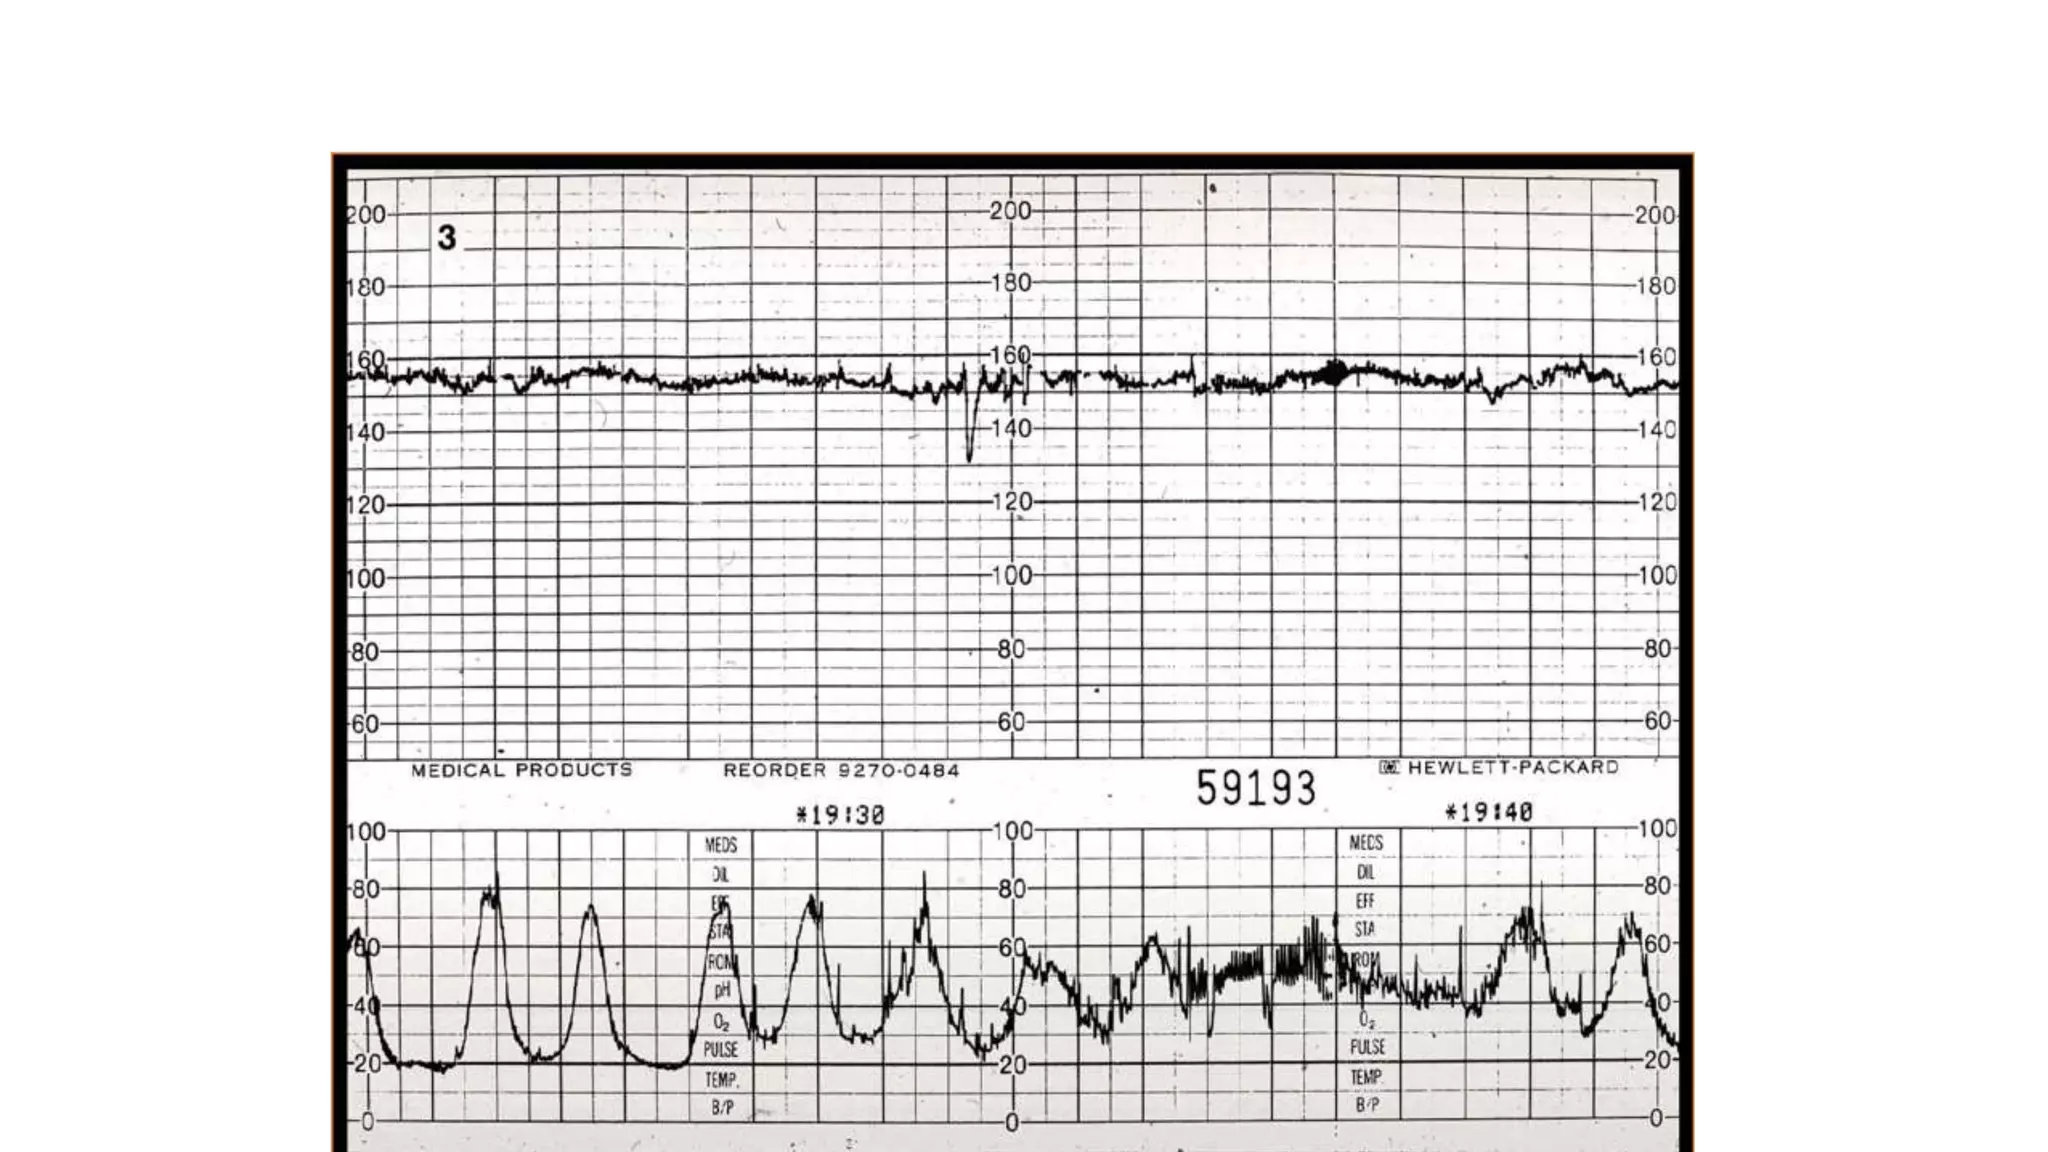

The document discusses key metrics for monitoring a baby's heart rate in utero, including the normal baseline rate of 100-160 bpm and variability. It also covers types of accelerations and decelerations that can occur, such as early or late, as well as bradycardia, which is an abnormally slow heart rate.